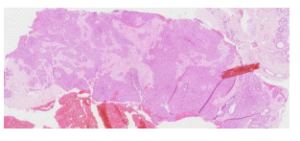

Fig1. Core biopsy of breast mass showing multiple expanded and anastomosing ducts with florid UDH-like epithelial proliferation

Introduction: Infiltrating epitheliosis (IE) of the breast is a complex sclerosing lesion rarely encountered in routine diagnostic practice. Histologically, all cases demonstrate florid usual ductal hyperplasia-like proliferation with irregular epithelial foci that appear to infiltrate into the adjacent scleroelastotic stroma. IE can easily be misdiagnosed as invasive carcinoma due to its infiltrative growth pattern and focal loss of myoepithelial cells. Most pathologists categorise IE in the radial scar/complex sclerosing lesion spectrum. Although association with

oncogenic PIK3CA 2,3 mutations has been found, its propensity to behave as a neoplastic proliferation is still

uncertain. It is currently regarded a florid hyperplastic entity requiring complete excision. Further studies are

needed to clarify its behaviour, association with carcinoma and its potential as a precursor lesion. Given its rarity and potential for misdiagnosis, recognising its subtle but distinctive features is essential. We report a case, aided by immunohistochemistry, that showcases these key histological features.